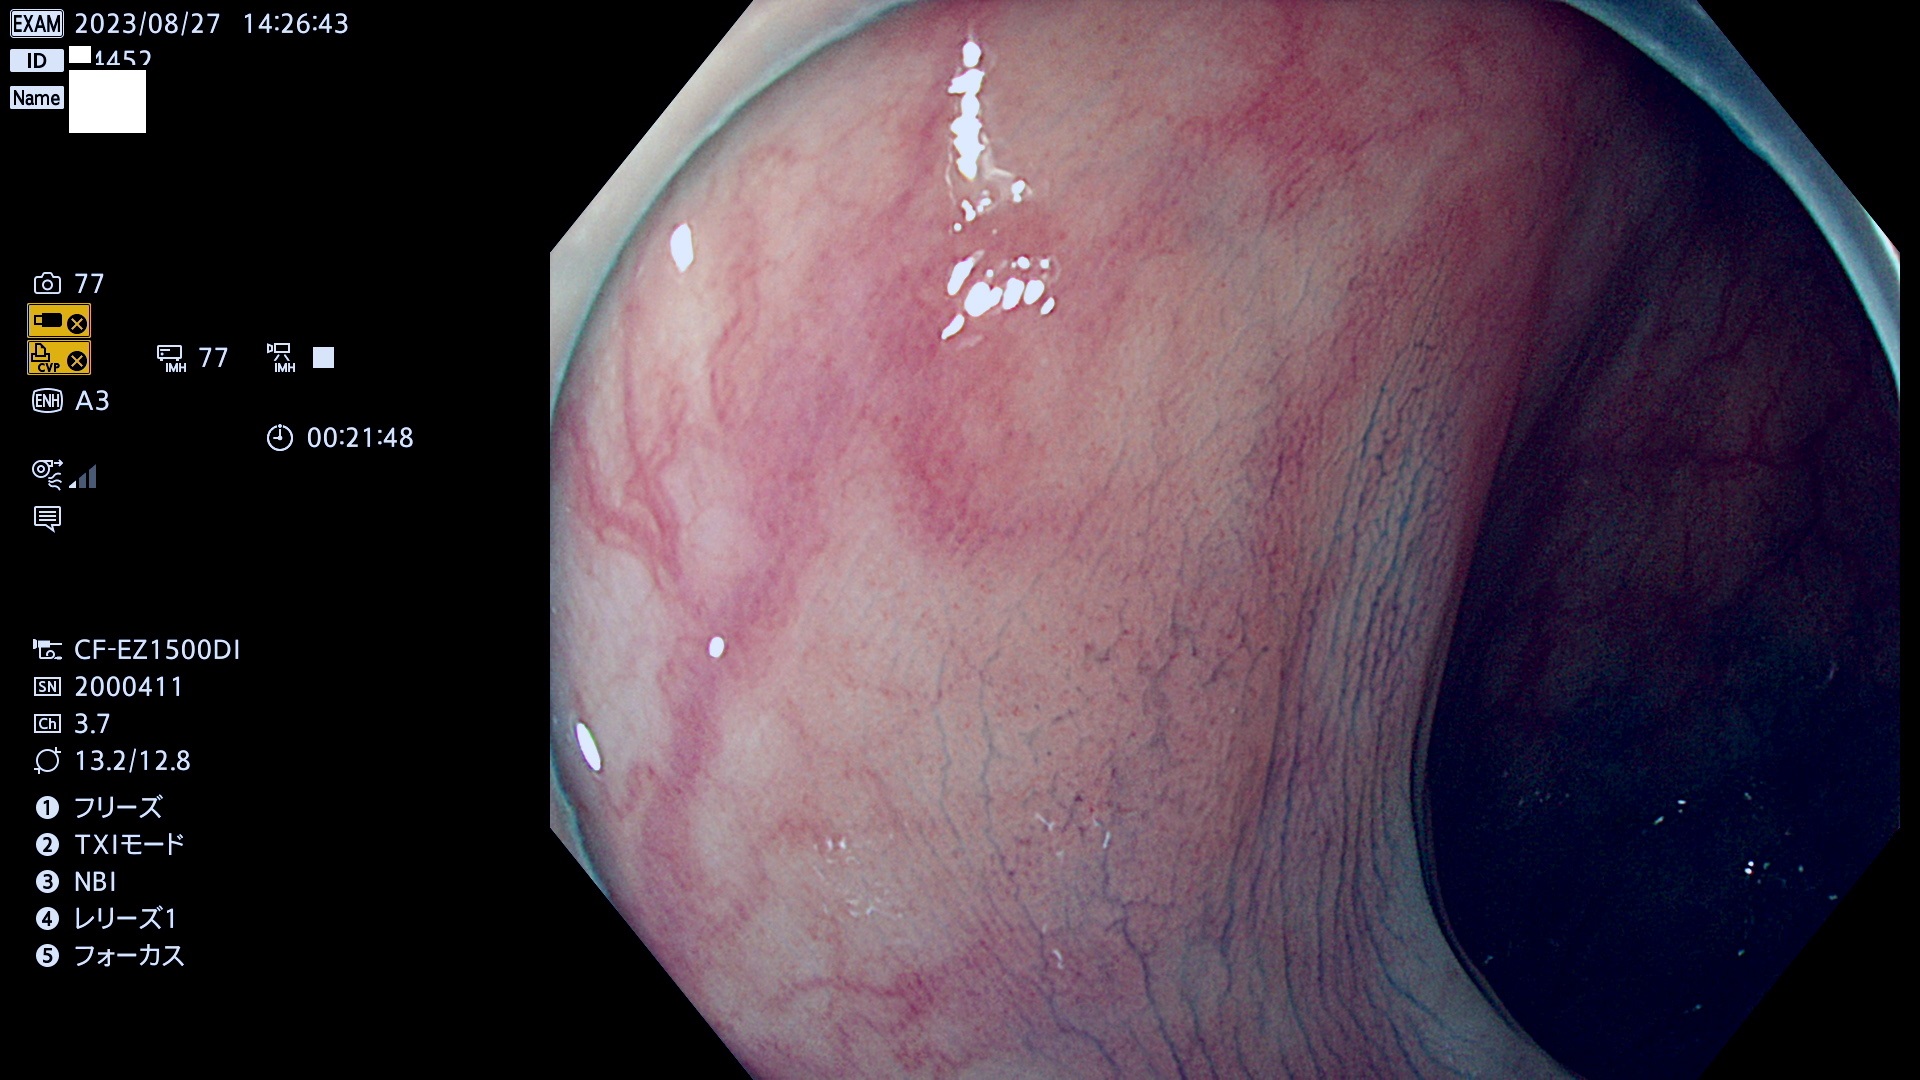

表面型腺腫(Flat Adenoma)の中で、完全に平坦な物をUb、陥凹している物をUcと呼びます。平坦隆起型(Ua)よりも、発見が難しく危険な病変です。このタイプは「内視鏡後・大腸癌の重要犯人」であり、この発見率は「腺腫発見率」よりも、重要な意味があります。

毎週の検査(木・金・土・日)に発見されたUb、Uc型・腺腫を、その週の日曜の夜にUPし1週間、提示します。

抽出の対象期間 2023年8月24日(木)〜8月27(日)の4日間(48件の検査)9件